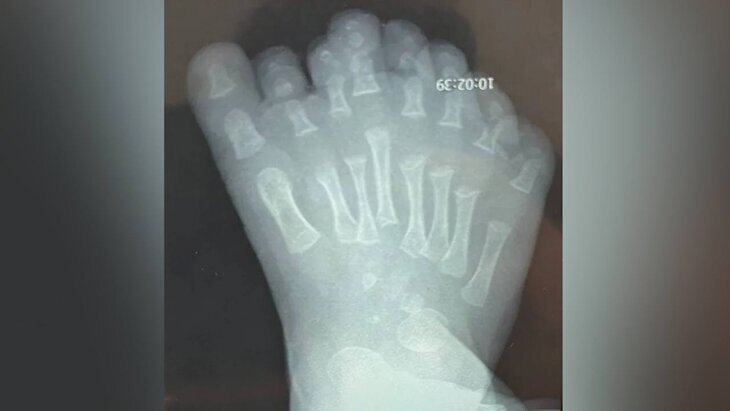

Фото: Ивано-Матренинская детская клиническая больница

С самого рождения ребенок имел восемь пальцев на правой ноге. Кроме того, у младенца было увеличено число плюсневых костей, что могло вызвать различные нарушения строения стопы.

Изучив специфику кровоснабжения стопы пациента, медики приняли решение удалять сверхкомплектные фаланги и плюсневые кости, начиная со второго, а затем третьего и четвертого пальцев. Этот подход позволяет сохранить функциональность ноги и восстановить ее естественные размеры без чрезмерного повреждения тканей.